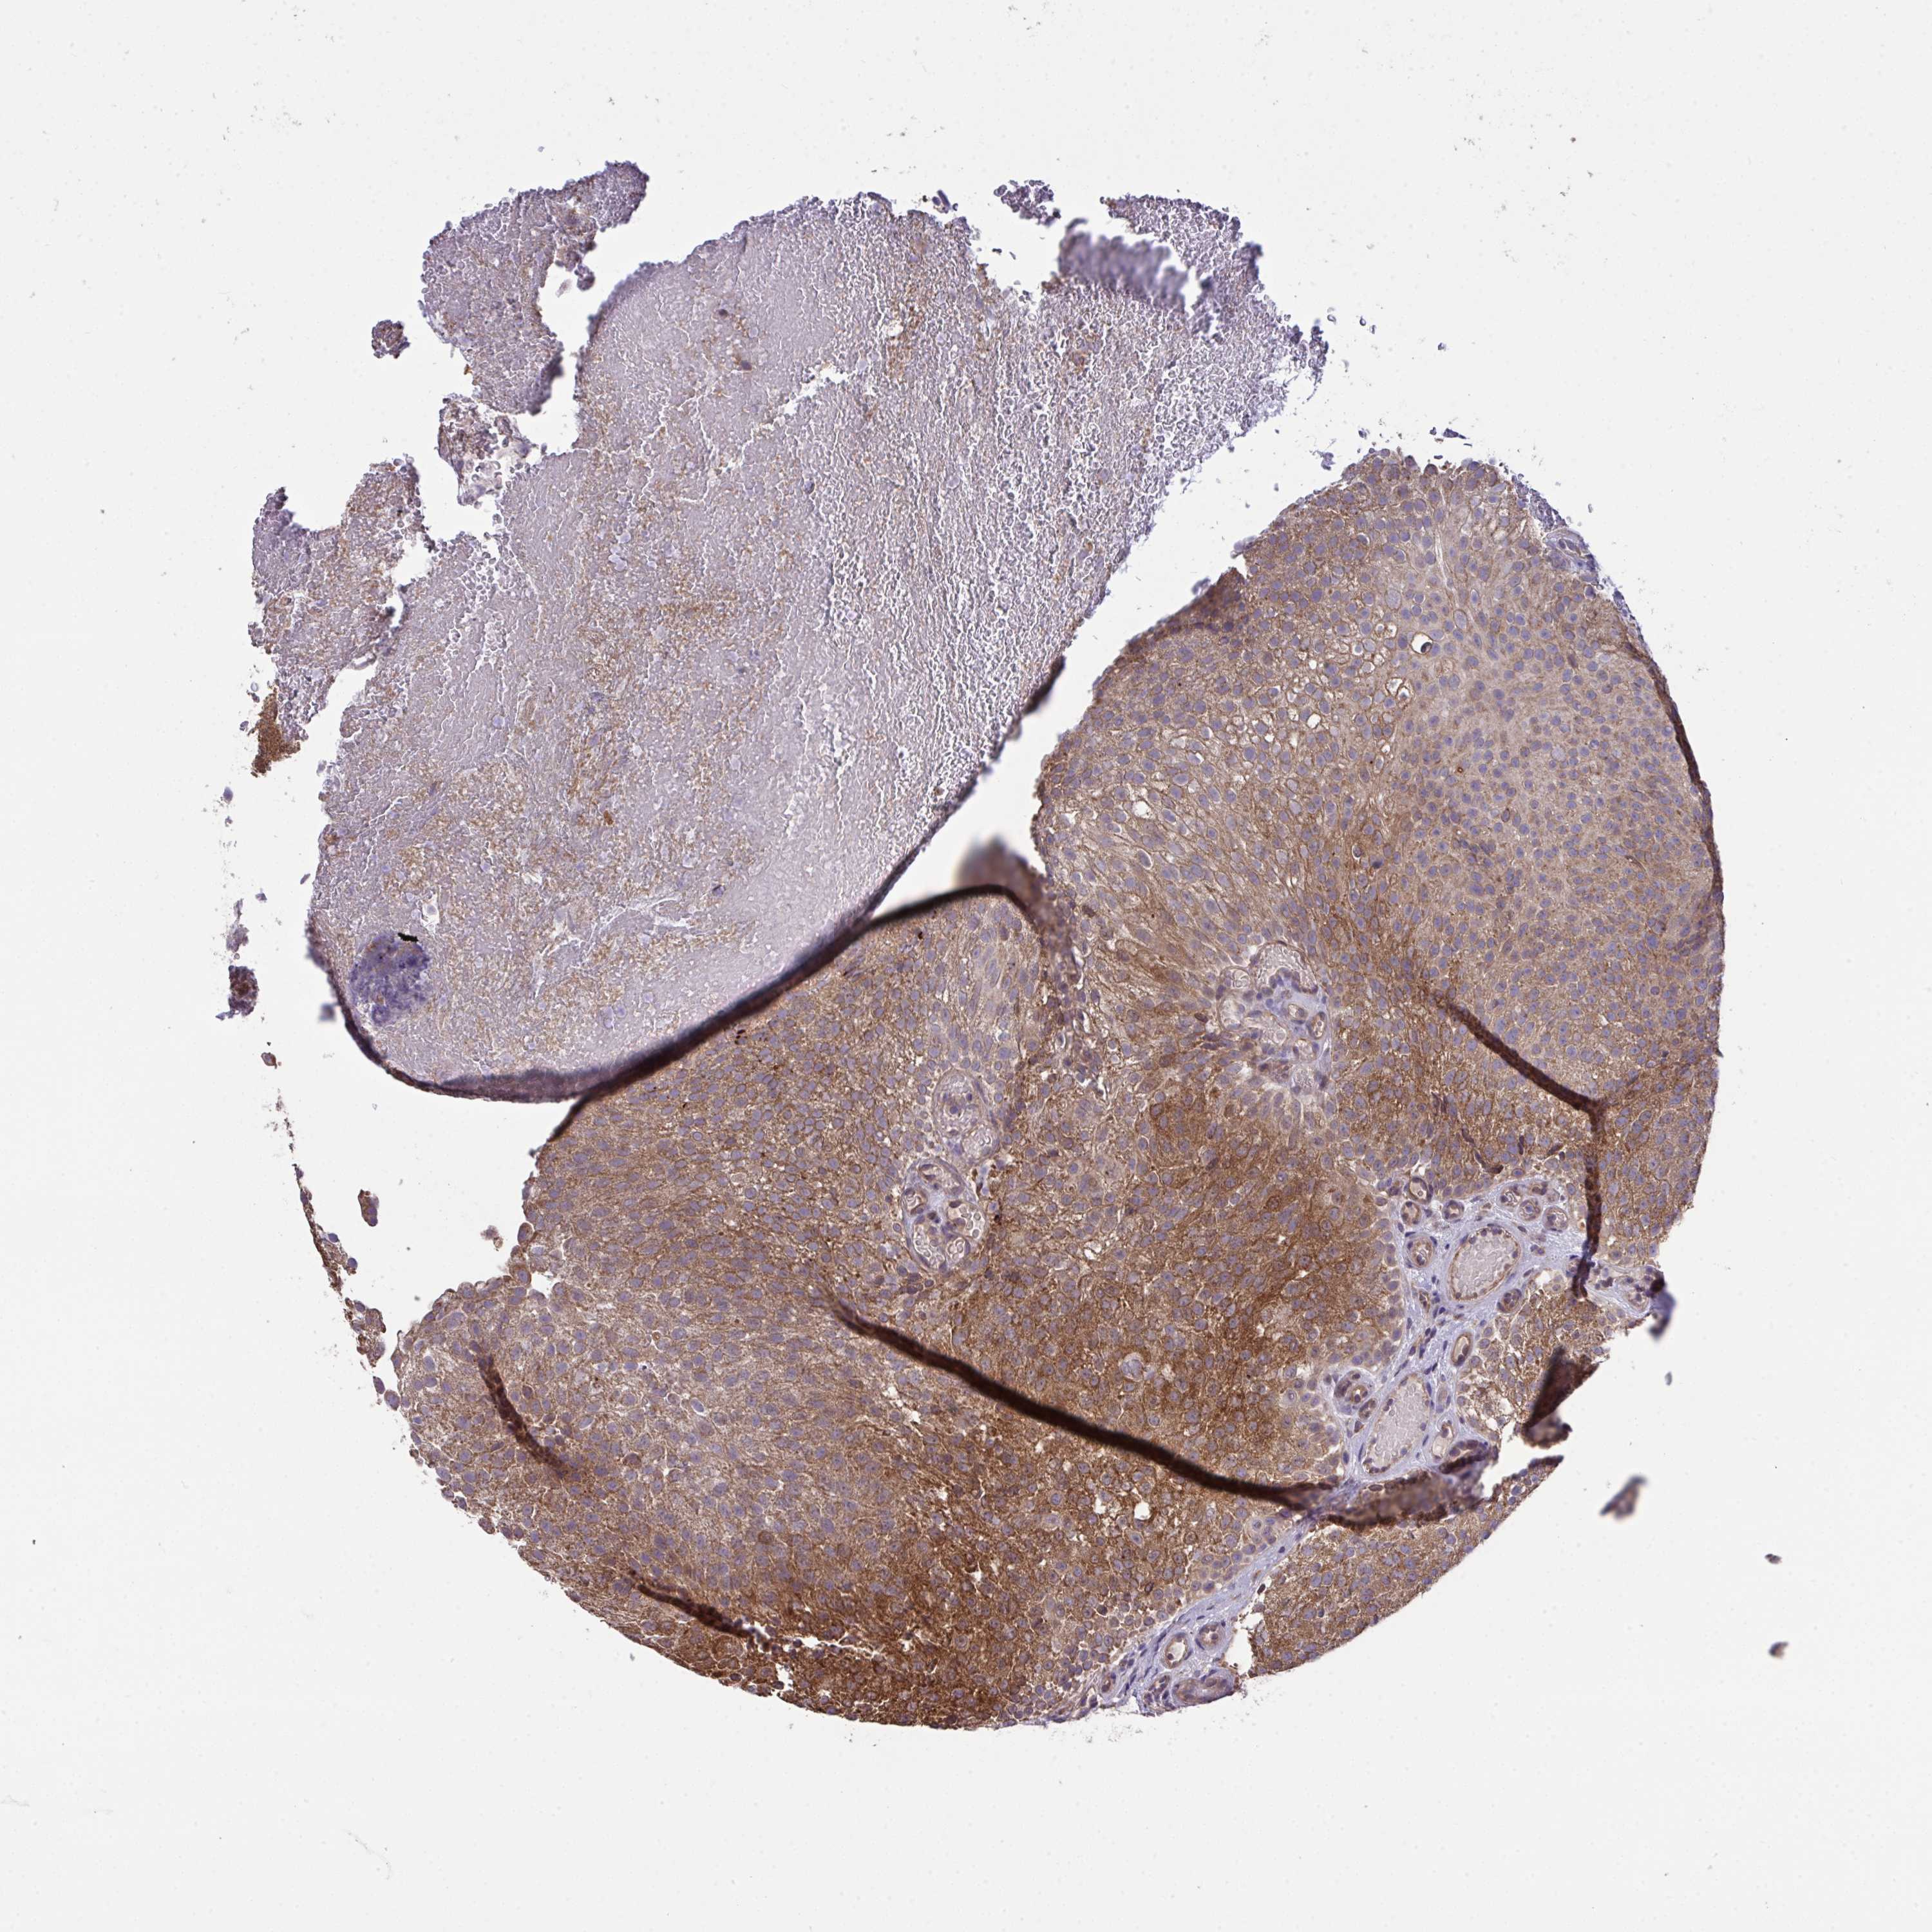

UROTHELIAL CANCER - Protein expressioni

A mouse-over function shows sample information and annotation data. Click on an image to view it in a full screen mode. Samples can be filtered based on level of antibody staining by selecting one or several of the following categories: high, medium, low and not detected. The assay and annotation is described here.

Note that samples used for immunohistochemistry by the Human Protein Atlas do not correspond to samples in the TCGA dataset.

Antibody stainingi

Antibody staining in the annotated cell types in the current human tissue is reported as not detected, low, medium, or high, based on conventional immunohistochemistry profiling in selected tissues. This score is based on the combination of the staining intensity and fraction of stained cells.

Each image is clickable and will lead to virtual microscopy that enables deeper exploration of all samples and also displays staining intensity scores, fraction scores and subcellular localization as well as patient and tissue information for each sample.

Antibody HPA044244

Antibody HPA058777

Antibody CAB020694

Staining

High

Medium

Low

Not detected

Intensity

Strong

Moderate

Weak

Negative

Quantity

>75%

75%-25%

<25%

None

Location

Nuclear

Cytoplasmic/membranous

Cytoplasmic/membranous,nuclear

Urothelial carcinoma, High grade

Urothelial carcinoma, Low grade

Urothelial carcinoma, NOS